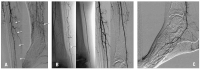

Ischämie

Abbildung 2a-b: A. Kritische Ischämie bei Verschluß der A. tibialis anterior und posterior sowie hochgradiger Stenosierung der A. fibularis (Pfeile). B. Ergebnis nach Laserrekanalisation der A. fibularis (1,7 mm Excimer-Laser) ohne Nachdilatation.